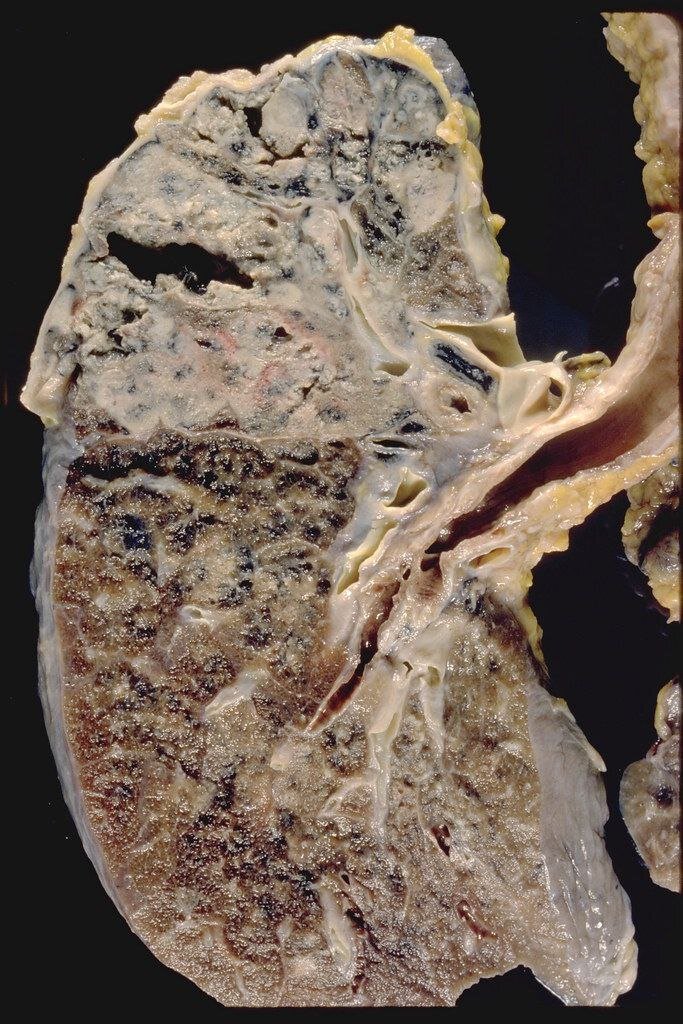

В основном палочка Коха поражает легкие и мочеполовую систему, но может также поражать кости, почки, цнс и кожу. Поэтому все виду туберкулёза делятся на легочный и внелегочный.

- гранулема разрушается, микобактерии выходят наружу, на этой стадии макрофаги уже не могут справиться с палочками Коха, и их размножение становится неконтролируемым. В итоге воспалительная реакция распространяется на все легкие и начинается Казеозный некроз (лат. caseosus — «творожистый») — форма смерти тканей, представляющая собой творожистую массу, которая состоит из иммунных клеток, погибших клеток легких и колоний туберкулезных бактерий.